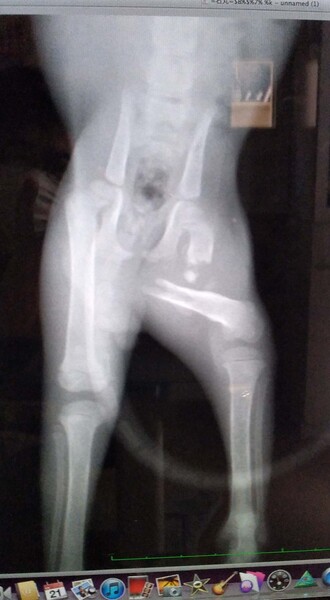

| その他(譲渡条件など) | 二匹のうちクリーム色の子猫は健康状態もよく元気です。 キジ子猫は少し後ろ左足をびっこをひいていましたので病院で診察したら大体部分を骨折していました。それをご理解いただいたうえで治療していただき育てて頂ける方がいたら幸いです。 |